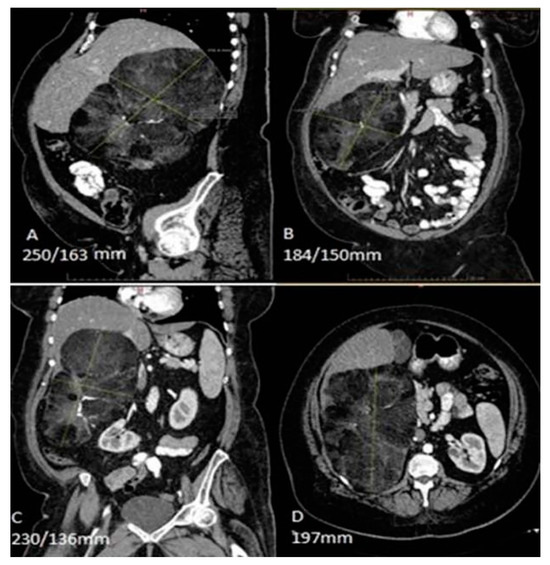

In our patient, the CT scan demonstrated a 25 cm x 17 cm x 21 cm well-delimitated, heterogenic, non-iodophil retroperitoneal tumor (Figure 1) in close contact with the right hepatic lobe, inferior vena cava, ascendant and transverse colon. The right kidney was medially and inferiorly displaced by the tumor volume (approx. 0,9 dm3).

Figure 1. Abdominal computed tomography scan demonstrating a 25 cm x 17 cm x 21 cm, mass in close contact with the right hepatic lobe, the inferior vena cava, the ascendant and transverse colon, and the diaphragm, and a medially and inferiorly displaced right kidney.